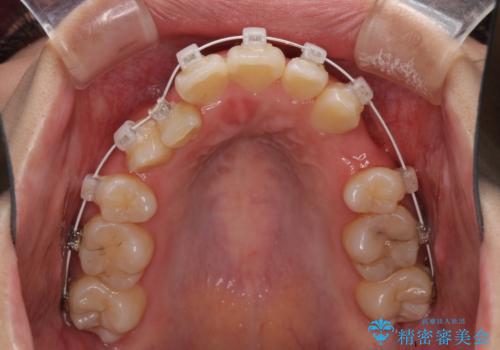

- 矯正装置

- 審美装置

- 八重歯を気にして来院された患者様です。

上下ともに前突感と叢生が認められ、上顎の正中が著しく右側にずれていたため、上下左右第一小臼歯4本を抜歯し、ワイヤー矯正にて治療を行うこととしました。

移動量が多かったため、治療期間は通常より半年~1年ほど長くかかりましたが、上下の正中をほぼ同じ位置にまで移動させることができました。